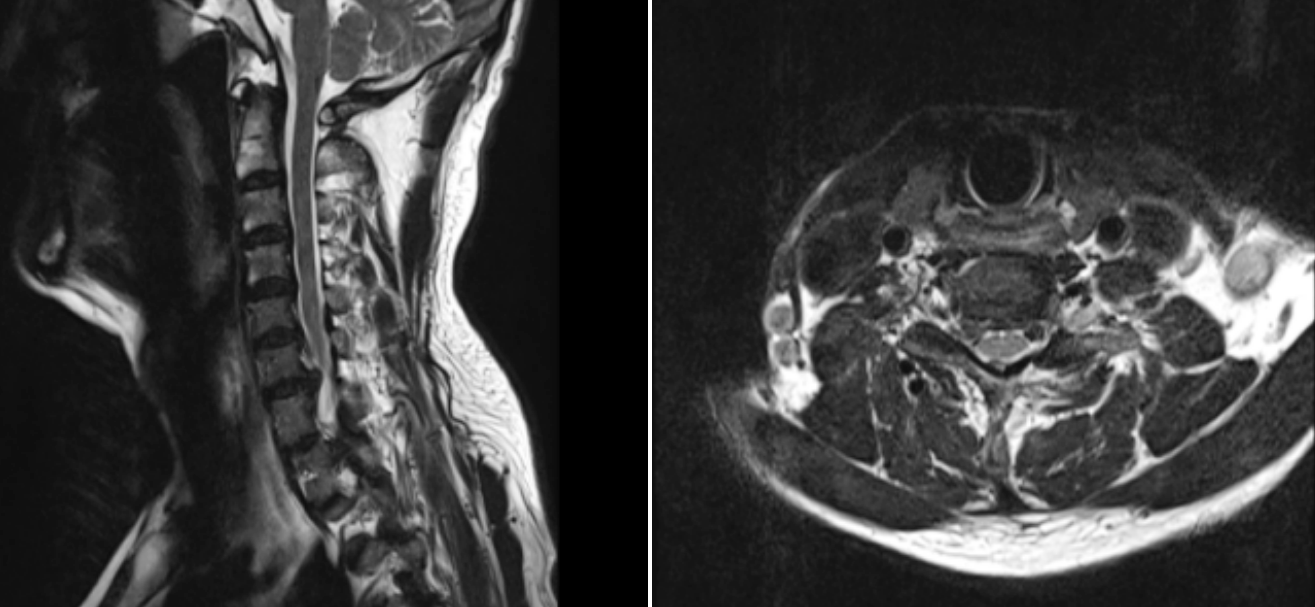

患者,男,65歲,近期飽受右側上肢疼痛與麻木之苦,歷時三周之久。在外院嘗試保守治療措施,效果不佳,來我院就診。經(jīng)過醫(yī)療團隊周密而細致的檢查,患者被明確診斷為“神經(jīng)根型頸椎病”,精準地指出了其癥狀的根本原因。

術前MRI圖像

鑒于患者病情的特殊性及復雜性,脊柱外科的朱中蛟專家團隊迅速行動起來,依托前沿醫(yī)療技術,精心制定了治療方案。團隊決定采用當前先進的UBE(單側雙通道脊柱內(nèi)鏡)技術,實施一場被譽為“鑰匙孔手術”的微創(chuàng)手術。此技術以其創(chuàng)傷小、恢復快的優(yōu)勢,成為治療此類頸椎疾病的理想選擇。